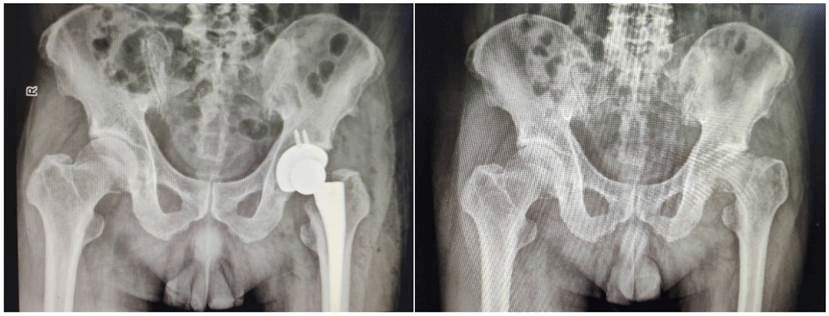

经过仔细评估,由于患者多年锻炼,肌肉强壮,而且在股骨头坏死后,股骨头明显塌陷,因此患肢短缩严重,经组内讨论,王文波教授决定行微创前路人工全髋关节置换术,在保持人工关节稳定性的同时,恢复患肢肢体长度。王文波教授为患者制定了详细的手术计划及充分的术前准备,入院次日便为患者行手术治疗。

术中,王文波主任与担任治疗组长的张涛副主任医师熟练的通过髋关节直接前方入路,在不破坏肌肉结构的情况下,显露病变的髋关节,应用其丰富的手术经验,顺利的取下已经严重变形的股骨头,并完成人工假体的植入操作。手术仅耗时1小时30分钟。术后,患者恢复良好,次日晨起即能下地行走,术后三日即顺利康复出院。